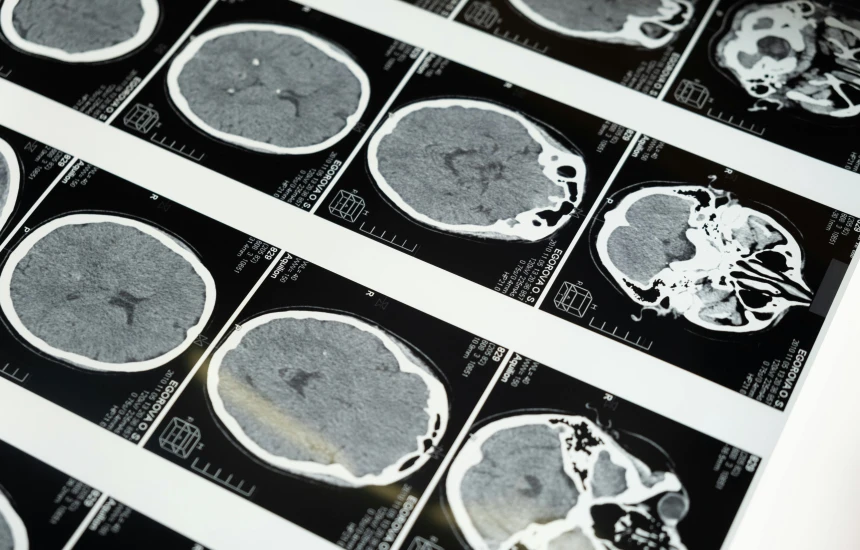

Në një studim të ri, të botuar në revistën Nature Neuroscience, teknologjia u testua te një grua 47-vjeçare me paralizë të katër gjymtyrëve, e cila nuk kishte folur për 18 vjet pas një sulmi në tru. Pajisja iu implantua në tru gjatë një operacioni klinik dhe lejonte përkthimin e synimit për të folur në fjali të rrjedhshme.

Shkencëtarët kanë regjistruar aktivitetin e trurit të gruas ndërsa ajo shqiptonte fjalitë në mendje. Ata përdorën një sintetizues që imitonte zërin e saj të dikurshëm dhe trajnuan një model të inteligjencës artificiale për t’i përkthyer sinjalet nervore në tinguj të të folurit.

Implanti është vendosur mbi qendrën e të folurit në tru dhe dërgon fragmente të vogla tingujsh çdo 80 milisekonda, afërsisht gjysmë rrokjeje, për t’u shndërruar në fjalë.